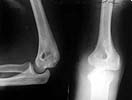

A female 48 years old sustained multiple injuries after fall from 5th floor 28/04/02. Among other injuries there was open posterior elbow dislocation (see attachment). It was reduced and the wound at the medial side of the joint debrided at the initial hospital. May 7 she was transferred to us. The wound healed primarily.

Yesterday (3 weeks post reduction) the plaster was removed to start motions. Gross elbow instability was revealed - the forearm easily can be displaced medially, and reduced back. Recent films with and without subluxation also attached.